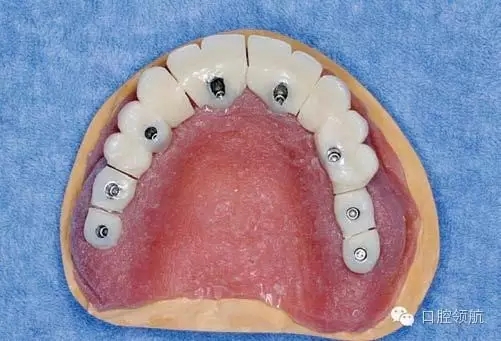

X線影像也未見異常(圖2)。

圖2 X線影像未見異常。